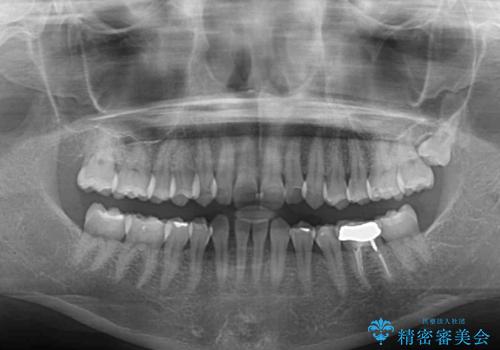

- 下顎前歯欠損による歯列不正を気にして来院された患者様です。

下顎の歯列が小さく、下顎前歯が隠れてしまう過蓋咬合(ディープバイト)であったため、

①下顎歯列を拡大し、欠損部に2歯分のインプラント補綴をおこなう

②上顎左右第一小臼歯2本を抜歯、下顎歯列を拡大し、欠損部に1歯分のインプラント補綴をおこなう

③上顎左右第一小臼歯2本を抜歯し、下顎はスペースを閉じる

のいずれかを提案しました。(①から③の順番にお勧めのプランとなります)

いずれもワイヤー矯正が望ましい治療方法ですが、家が遠方であり、近い将来出産される予定もあるとのことで、何とかマウスピース矯正でも対応可能な③にて治療を行うこととしました。